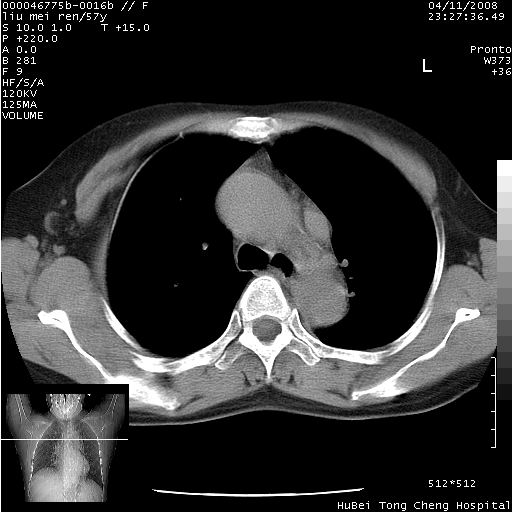

患者 女,57岁。因车祸受伤,其家属要求行“全身ct检查”。平素健康。

胸部ct轴位平扫(层厚10mm,螺距1.5,重建间隔10mm),图像如下:

左位上腔静脉,先天变异。

左位上腔静脉,先天变异。与双侧上腔静脉区别。